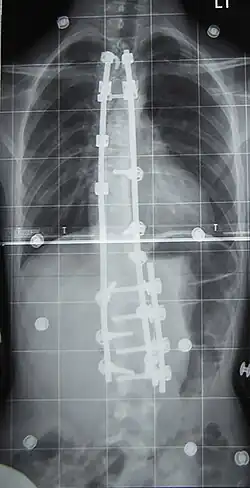

Fusión vertebral con instrumentación

La fusión espinal es la cirugía que más se realiza para la escoliosis. En este procedimiento, el hueso (ya sea cosechado en otras partes del autoinjerto cuerpo o de un injerto de donantes) es injertado en las vértebras de manera que cuando se cura se va a formar una masa ósea sólida y en la columna vertebral se vuelve rígido. Esto previene el empeoramiento de la curva a expensas de algunos movimientos de la columna. Esto puede ser realizado desde la anterior (frontal) los aspectos de la columna vertebral por entrar en la cavidad torácica o abdominal, o más comúnmente realizado desde la parte trasera (posterior). Una combinación se utiliza en los casos más graves.

Los sistemas modernos espinal están tratando de resolver el desequilibrio sagital y sin resolver los defectos de rotación por el sistema de barras de Harrington. Que implican una combinación de varillas, tornillos, ganchos y alambres de fijación de la columna vertebral y puede solicitar más fuerte, más seguro para las fuerzas de la columna vertebral de la barra de Harrington. Esta técnica se conoce como la Cotrel instrumentación Dubousset, actualmente la técnica más común para el procedimiento.